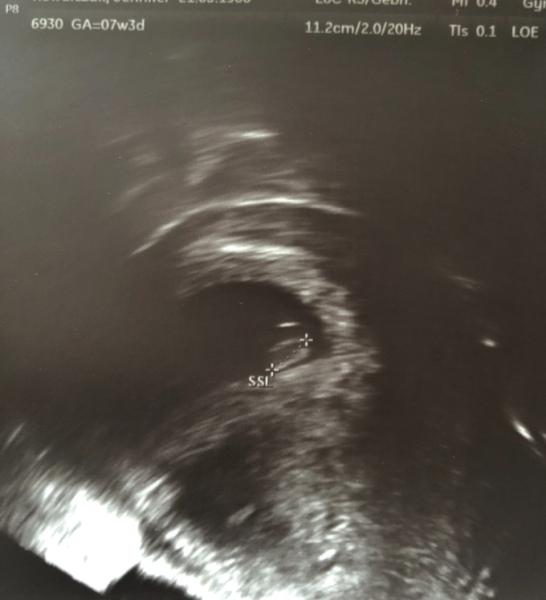

Hallo Zusammen, in den letzten Wochen habe ich mich hier ziemlich zurückgezogen, diese Warterei bis zum ersten Termin war furchtbar und ich hab mich total verrückt gemacht. Aber alles ist gut und da wo es hingehört und Herzchen hat geschlagen. Das Ultraschallgerät ist nicht das Beste, daher konnte sie auch nur mühsam messen. Laut der Messung ist es fast ne Woche zu klein, aber sie sagte auch, dass sie das erst beim nächsten Termin genauer sagen kann. Mädels, das werden wieder lange unerträgliche 4 Wochen. Beim nächsten Termin gibt es dann auch den Mutterpass. Blut wurde schon mal abgenommen (auch für Test auf Cytomegalie und Toxoplasmose).

Bild zu Zurück vom Arzt - Forum für April - Mamis